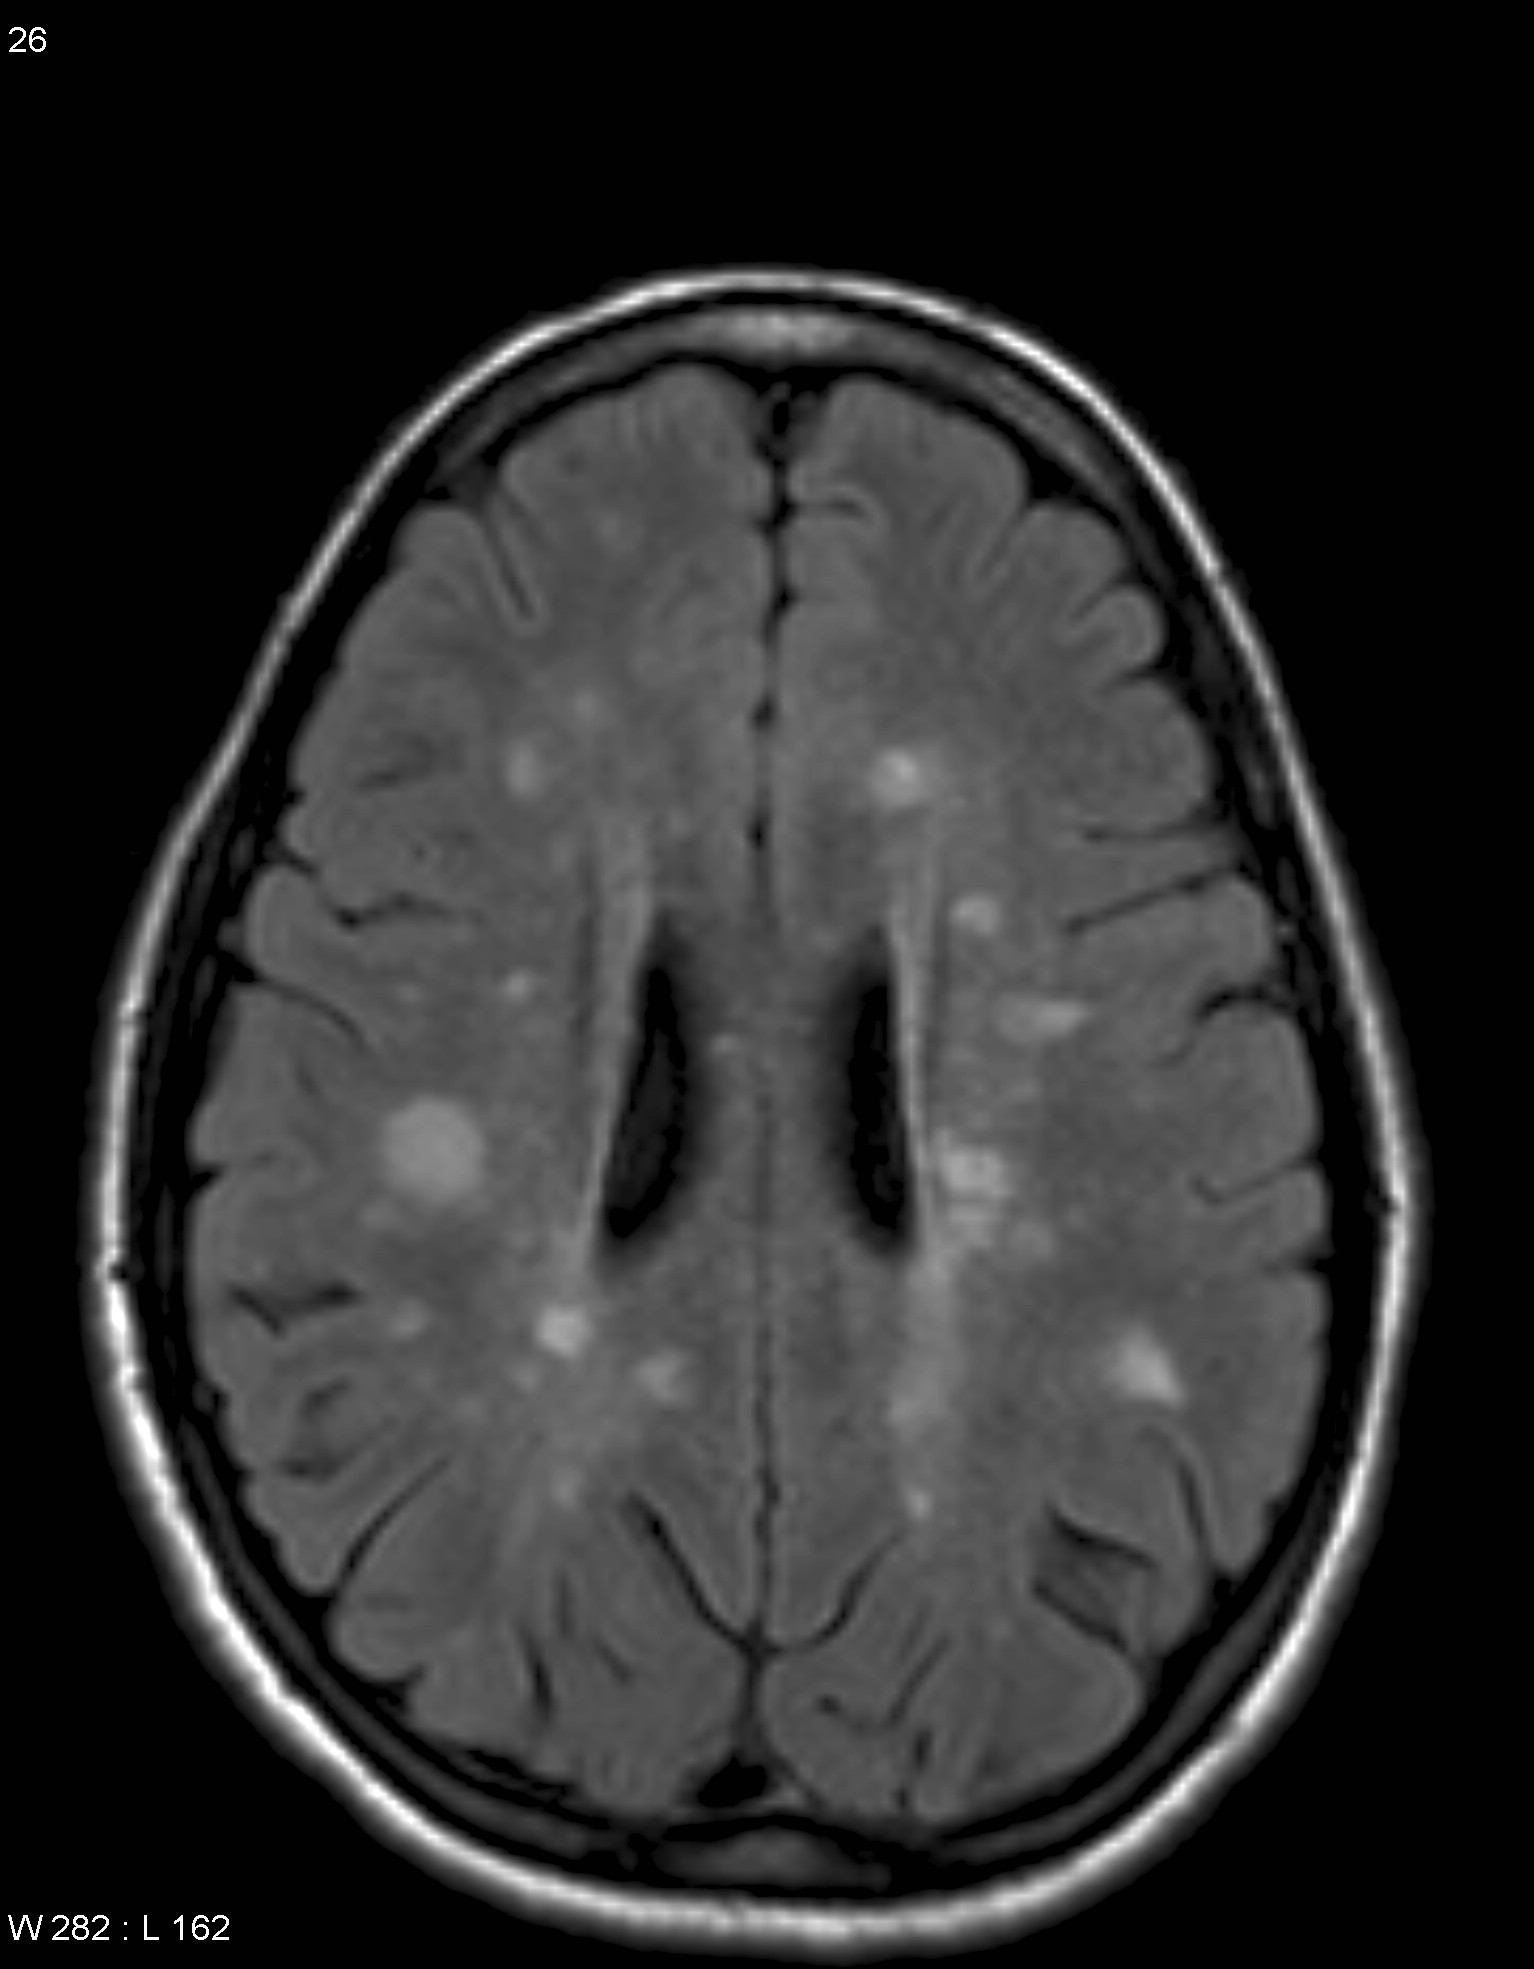

Иллюстрации и пояснения: гиподенсивный очаг на КТ головного мозга